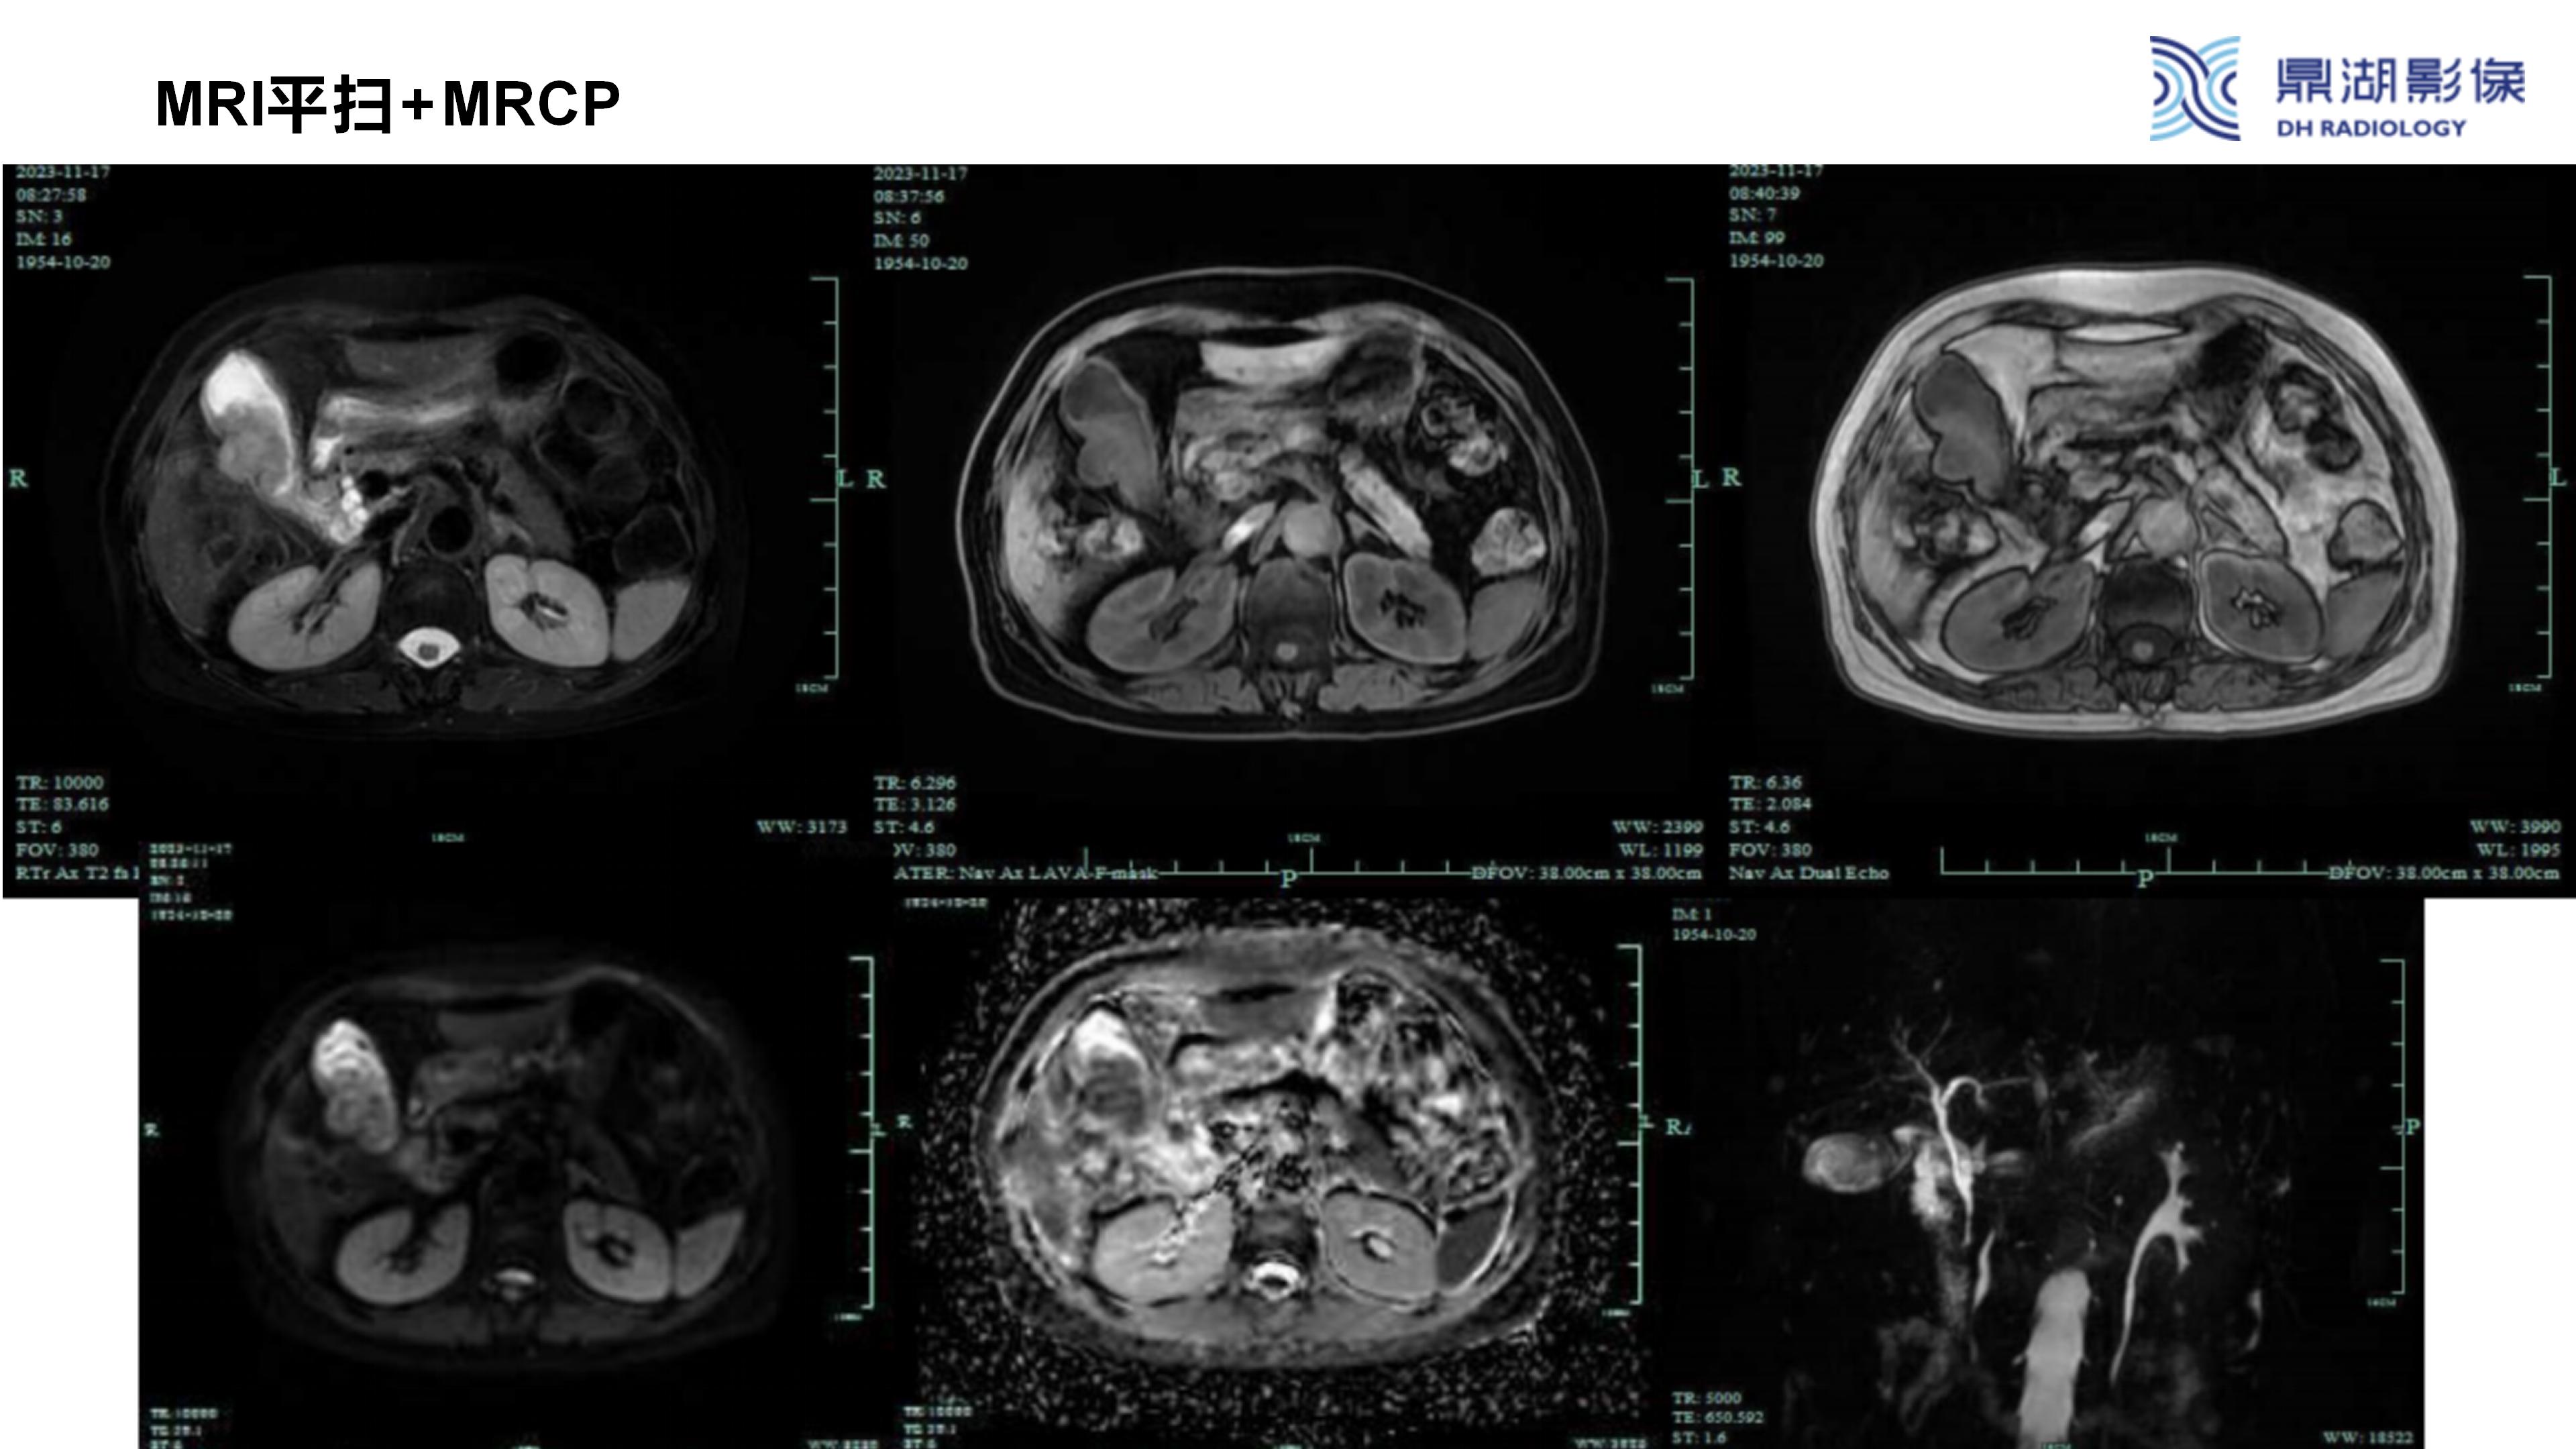

胆囊癌-鼎湖社群读片病例